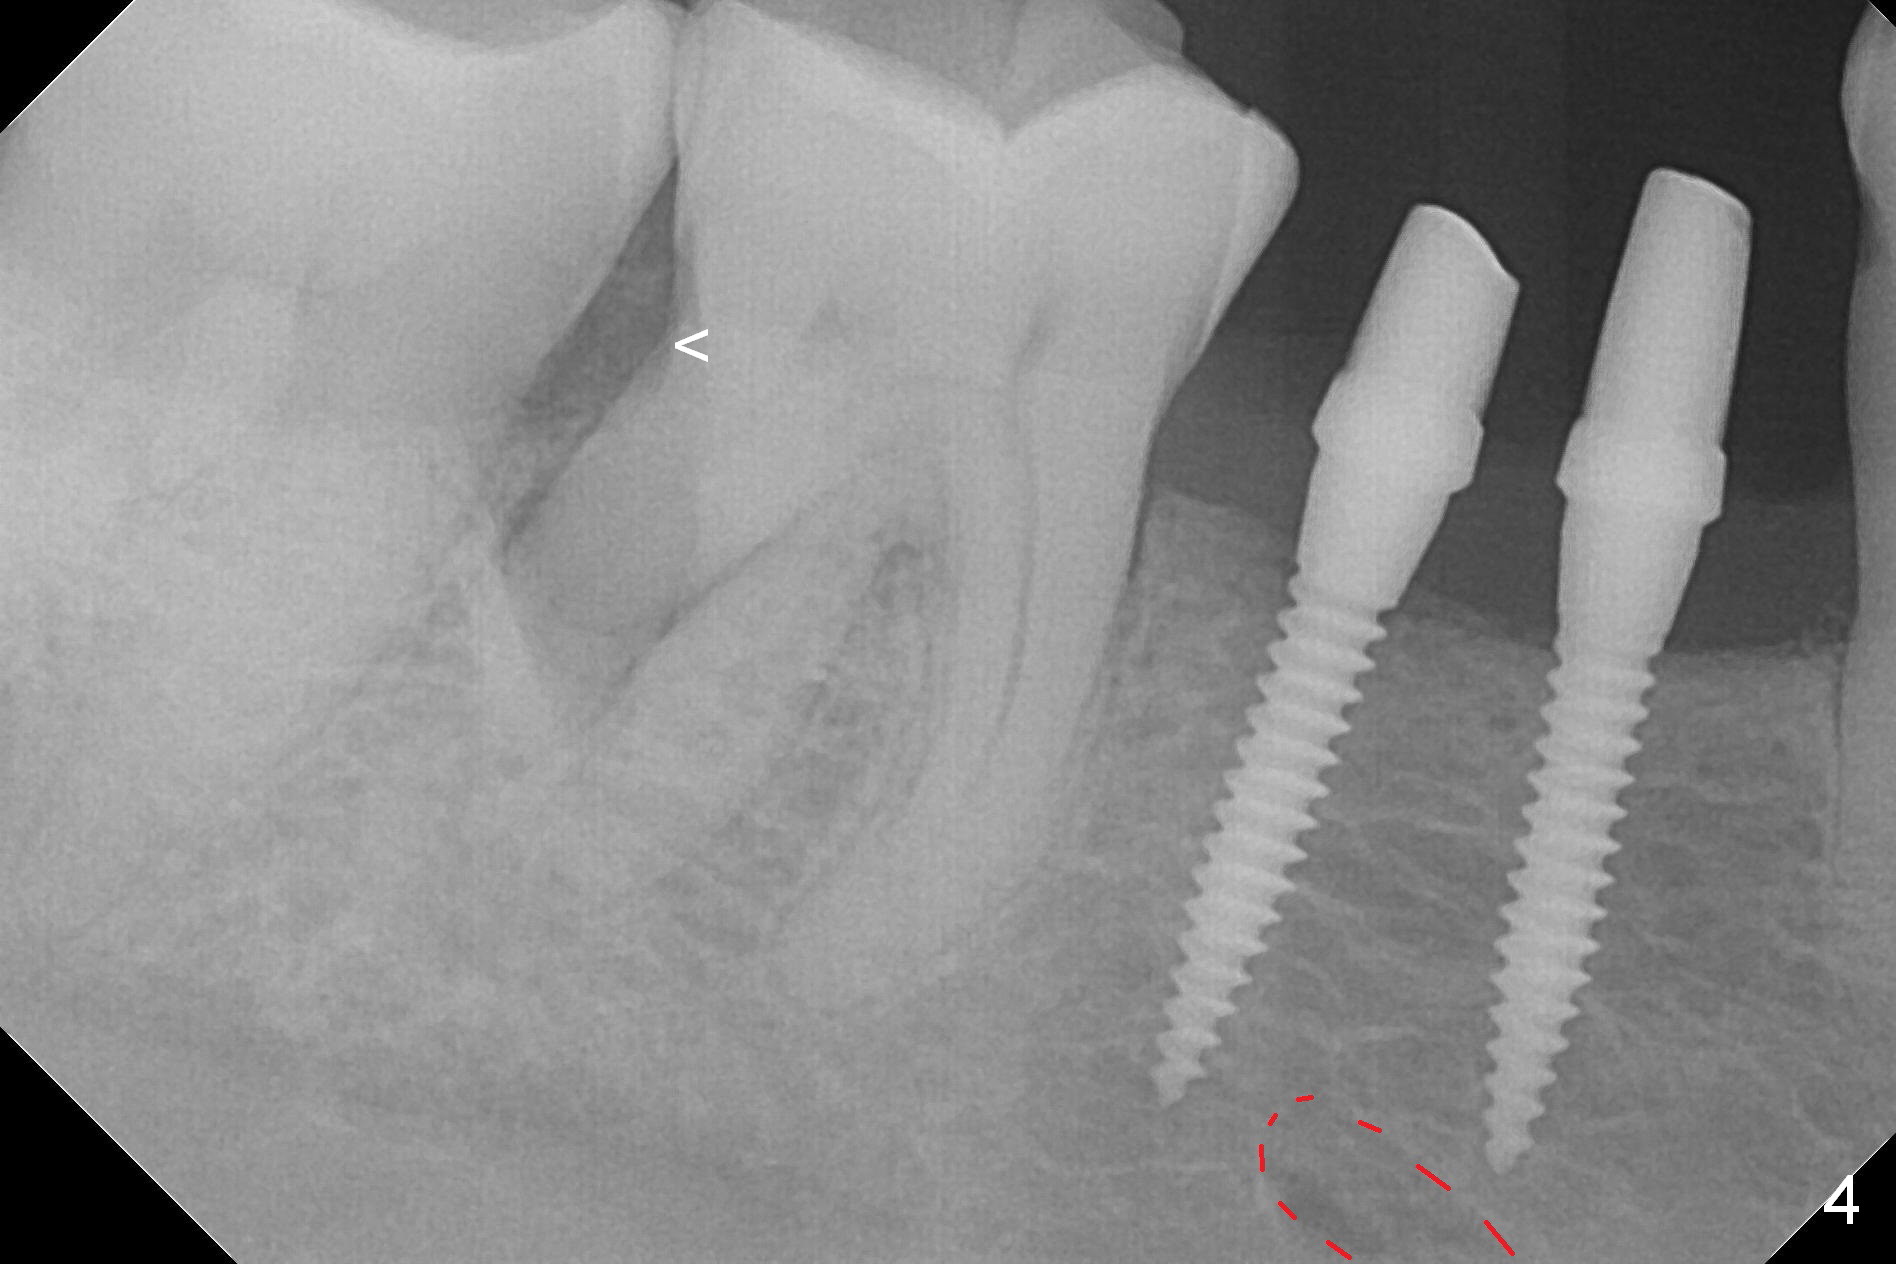

The wide mesiodistal space at #29 is most likely due to congenital missing permanent tooth (i.e., deciduous molar retention before extraction 34 years ago). The patient is now 62 years old. In fact the buccolingual width is not so narrow (Fig.1). After incision, the ridge is approximately 5 mm. Two osteotomies are established with 1.2 mm drill at 8 mm mesially and 1.5 mm one at 10 mm distally (Fig.2). The apparent approximation of the mesial osteotomy to the Mental Loop (red dashed line) is related to X-ray angulation, since there is 1-2 mm separation when two of 2x10(2) mm 1-piece implants are placed (Fig.3,4). Insertion torques of the mesial and distal implants are less than 25 and 15 Ncm, respectively. In fact bone graft is placed around the distolingual root of the tooth #30 after calculus removal (Fig.4 <). Following reduction of the abutments, periodontal dressing is applied locally. The dressing dislodged 13 days postop (Fig.5). A provisional is going to be fabricated 4 weeks postop when the wound heals (Fig.6). No bone loss is observed 4 months postop (Fig.7).